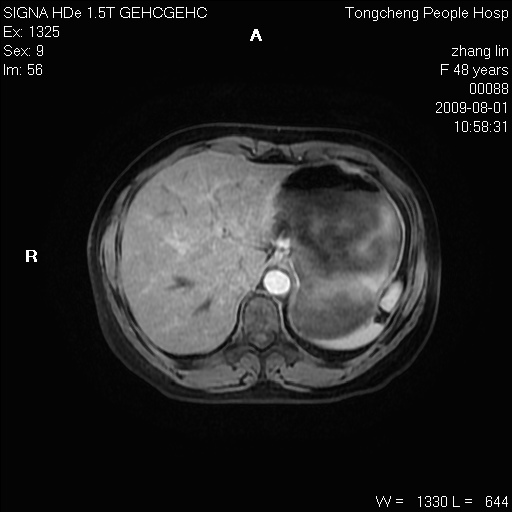

女,48岁。健康体检,彩超发现右肾占位性病变。平素健康。

临床诊断:右肾占位性病变,性质待定(囊肿?肿瘤?)。

上中腹部mr平扫+增强扫描,图像如下:

右肾上极见一类圆形病灶,t1wi呈等信号t2wi呈等高混杂信号,三期增强无强化,边界清---考虑囊肿出血。

同反相位均表现为等信号,病变无强化,考虑含蛋白的囊肿可能,弥散加权相或许有些帮助,